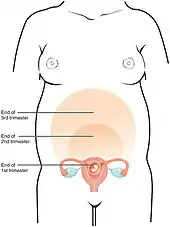

Trimesters

Pregnancy is divided into three trimesters, each lasting for approximately 3 months.[4] The exact length of each trimester can vary between sources.

- The first trimester begins with the start of gestational age as described above, that is, the beginning of week 1, or 0 weeks + 0 days of gestational age (GA). It ends at week 12 (11 weeks + 6 days of GA)[4] or end of week 14 (13 weeks + 6 days of GA).[31]

- The second trimester is defined as starting, between the beginning of week 13 (12 weeks +0 days of GA)[4] and beginning of week 15 (14 weeks + 0 days of GA).[31] It ends at the end of week 27 (26 weeks + 6 days of GA)[31] or end of week 28 (27 weeks + 6 days of GA).[4]

- The third trimester is defined as starting, between the beginning of week 28 (27 weeks + 0 days of GA)[31] or beginning of week 29 (28 weeks + 0 days of GA).[4] It lasts until childbirth.

Relative size in 5th month (simplified illustration) Relative size in 9th month (simplified illustration)

Relative size in 9th month (simplified illustration)